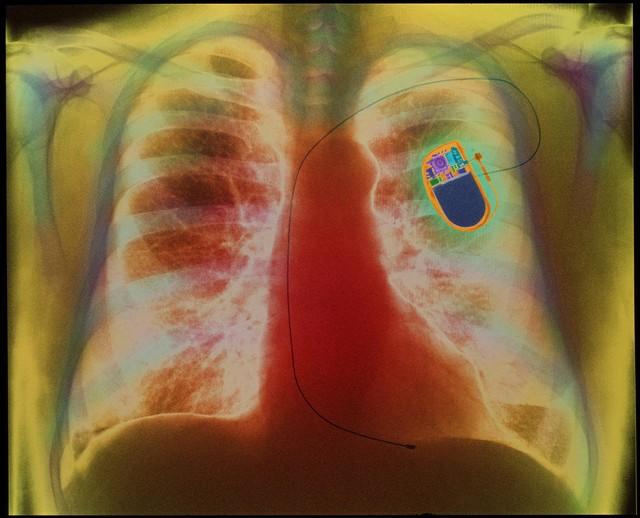

心律失常是导致心跳加速的常见原因之一。正常成年人的心率应在每分钟60到100次之间。当心脏跳动过快、过慢或不规则时,就被归类为心律失常。这种状况可能由多种因素引起,包括心脏病变、电解质不平衡或心脏结构异常。心律失常可能导致心脏泵血功能减弱,长期下去可能引发更严重的心脏问题。

心动过速,一种特定类型的心律失常,表现为心率异常增快。在不进行任何体力活动的情况下,如果你的心率持续超过100次/分钟,可ღ能就是心动过速的信号。此症状不应被忽视,因为它可能是心脏疾病如心肌炎、心肌梗死或心脏瓣膜病变的早期迹象。